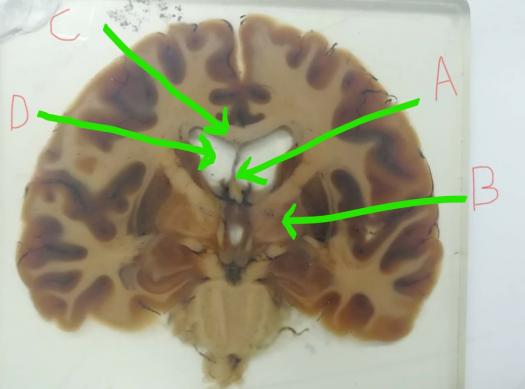

19. Identify the septum pellucidum :

Explanation

The septum pellucidum is a thin membrane located in the midline of the brain, separating the lateral ventricles. In this question, the correct answer is A, indicating that the septum pellucidum can be identified in that location.

6. Which letter indicates the styloid process ?

The letter B indicates the styloid process.

38. Identify the following structure:

The structure being identified is the cingulate gyrus. The cingulate gyrus is a part of the cerebral cortex and is located above the corpus callosum. It plays a role in various functions such as emotion regulation, decision-making, and attention. It is involved in the limbic system, which is responsible for emotions and memory.